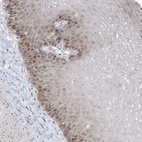

Immunohistochemical staining of human esophagus shows distinct nucleolar positivity in squamous epithelial cells.